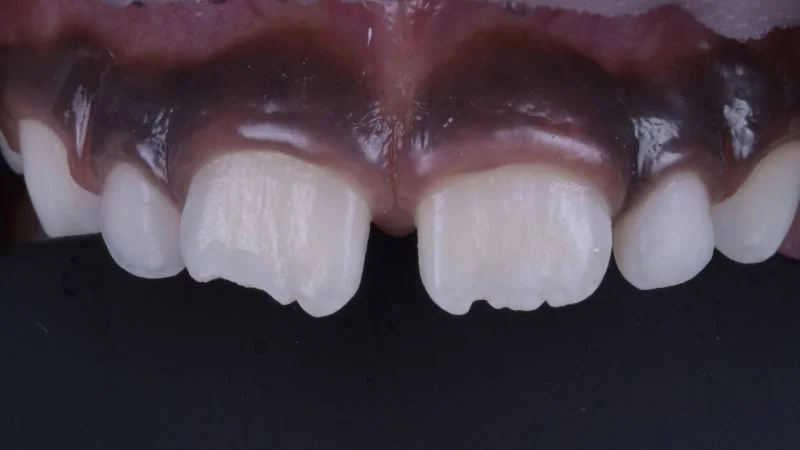

Restauration nach Fertigstellung.

Polierte Oberfläche der Restauration an Zahn 11. 3M Sof-Lex Ausarbeitungs- und Polierscheiben Medium, Fein, Superfein, Bimssteinpaste und Polierpaste kamen zum Einsatz. Die Ausformung der Inzisalkante erfolgte mit feinkörnigen rotierenden Instrumenten.